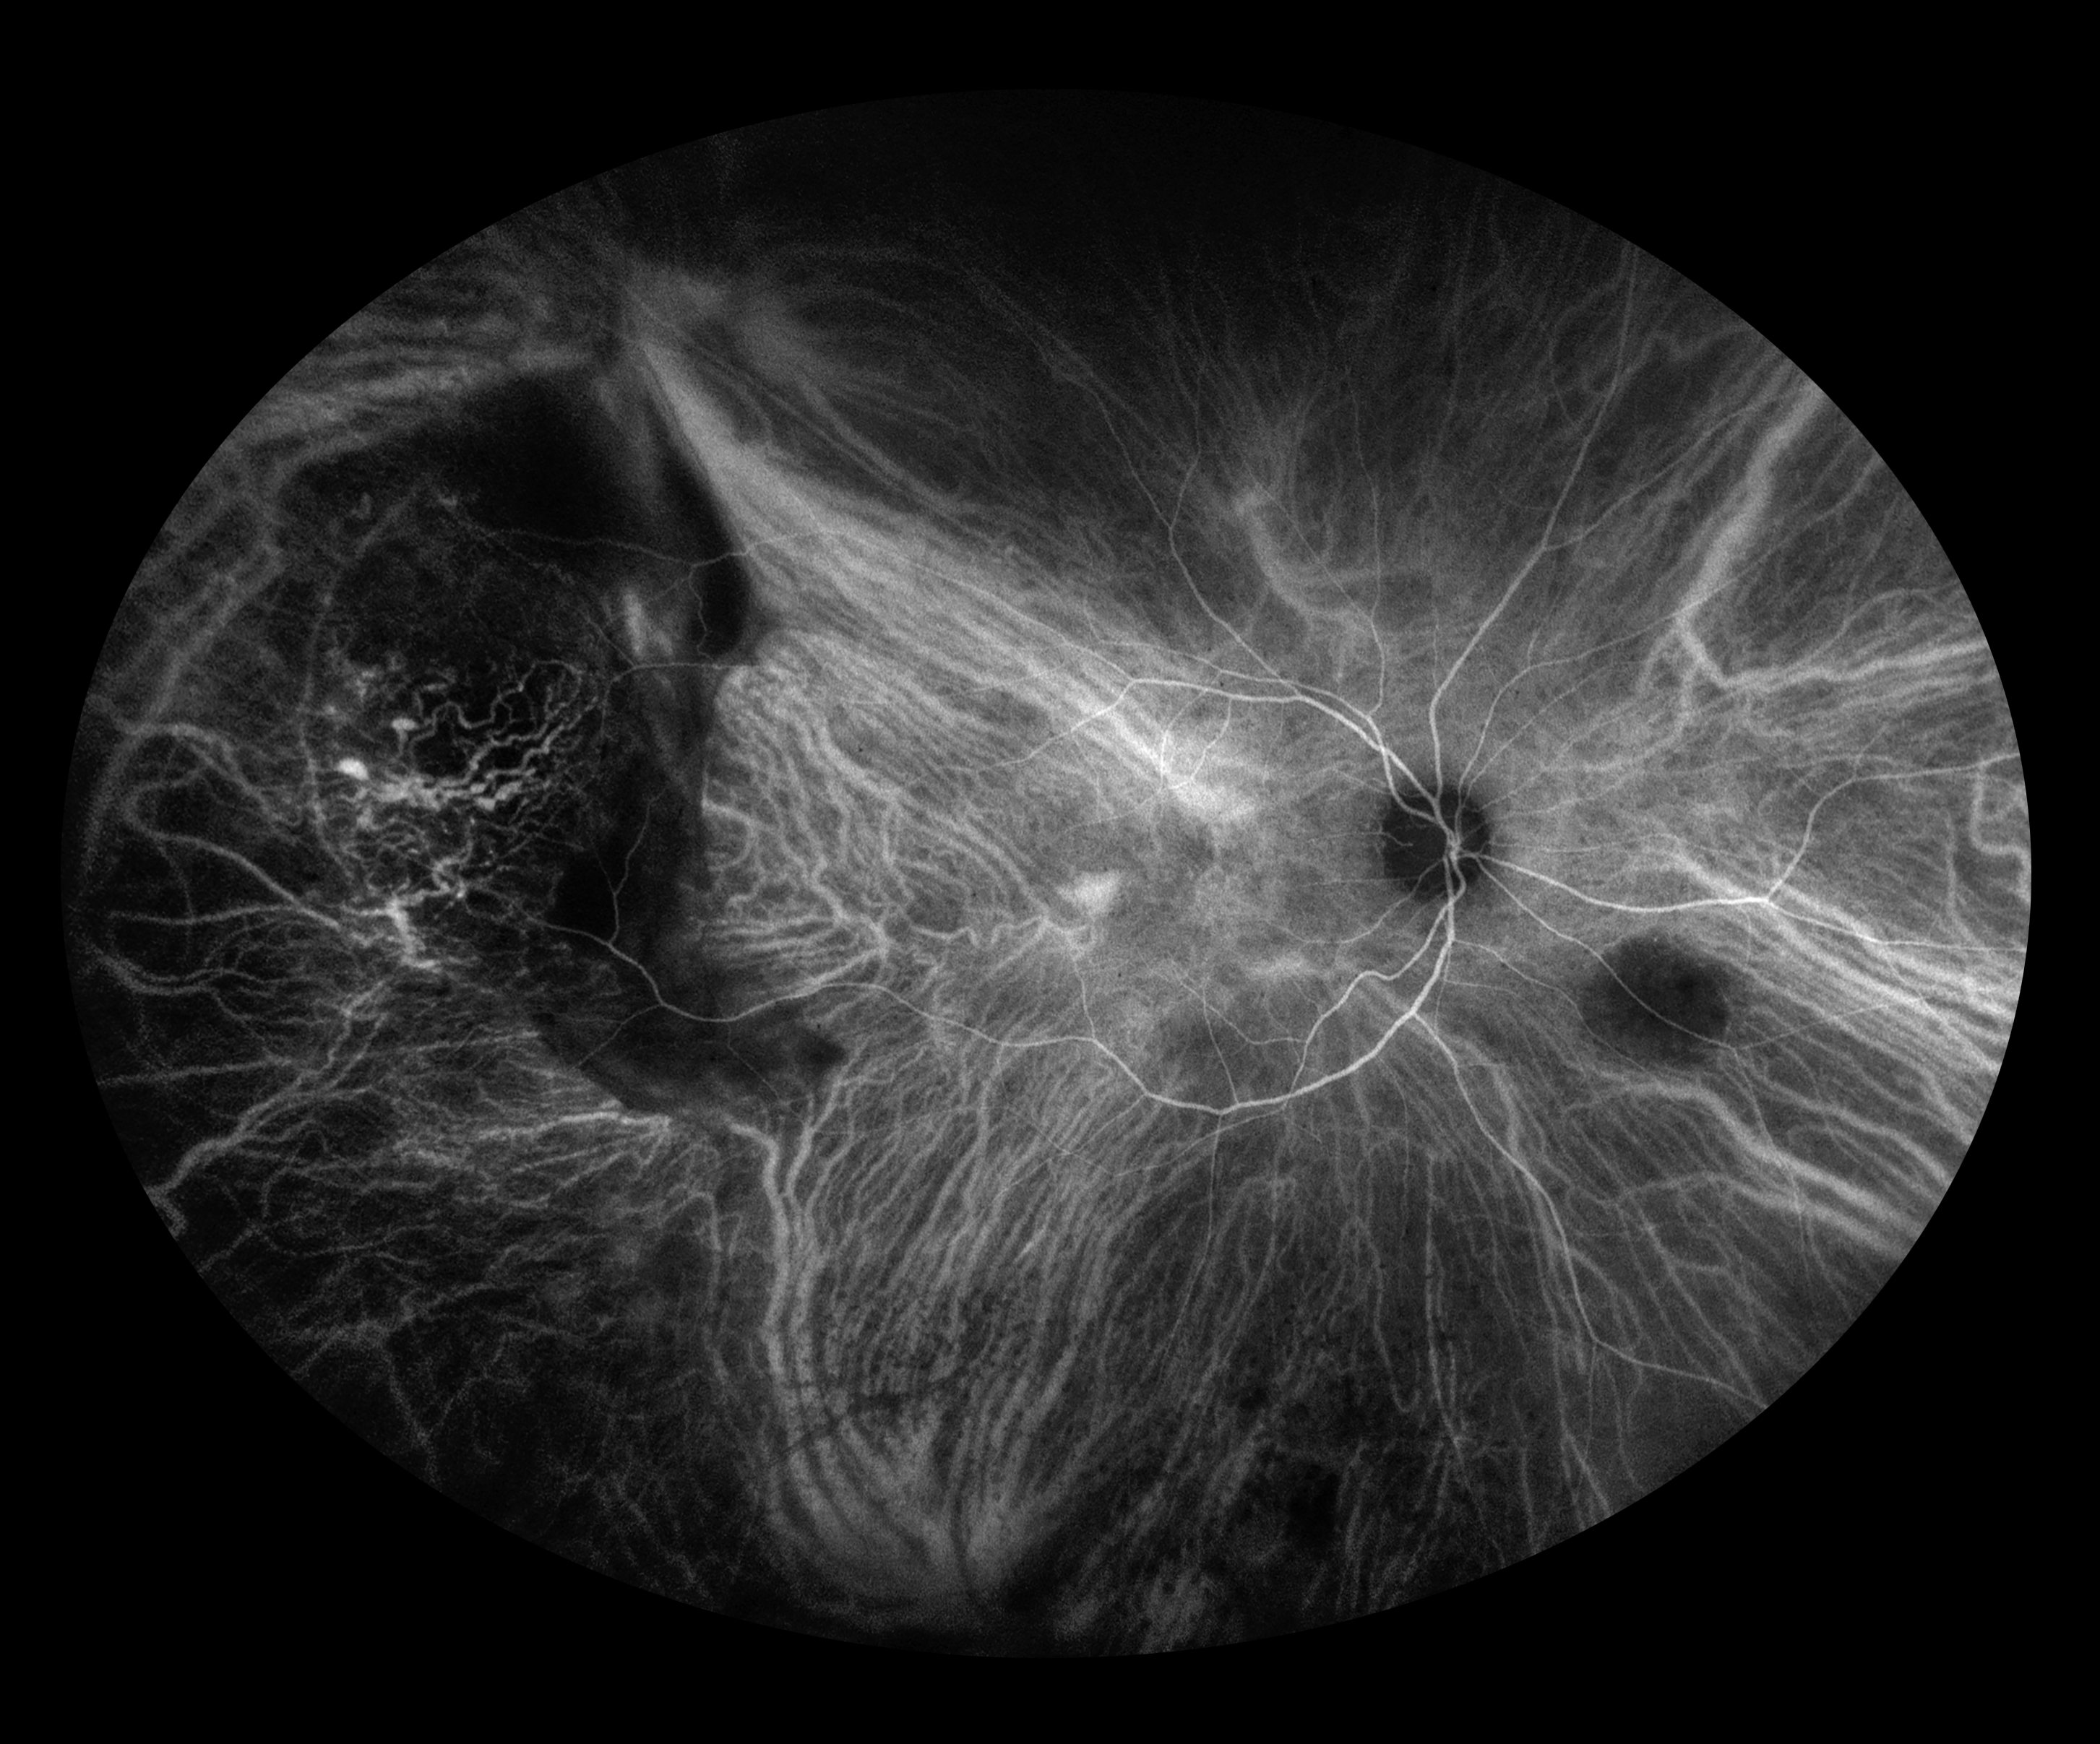

PECHR Presented by Judith Gulian, OCT-C This photograph received Second Place, Indocyanine Green Angiography in the 2025 OPS Scientific Exhibit. Filed Under Retina OPS Photo